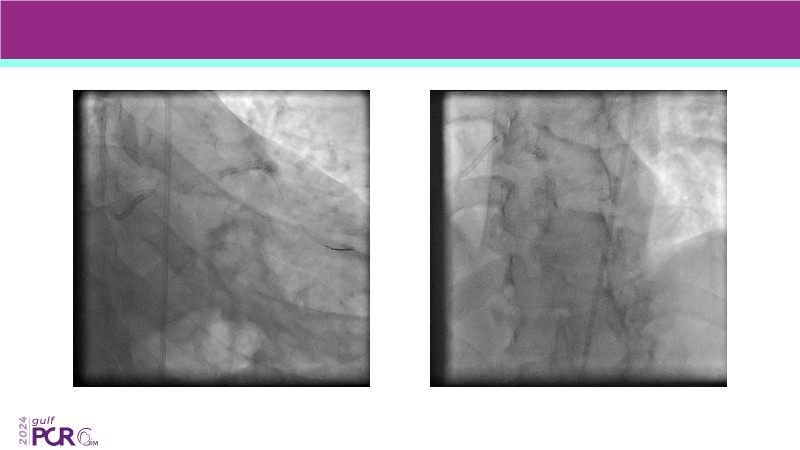

Explore the future of complex PCI with Meril Life’s advanced solutions. Learn about thin-strut platforms, dedicated stents for side branches and diffuse lesions, the role of drug-eluting balloons in metal-free PCI, and the clinical potential of the Myval THV technology.

- To achieve goals of metal-free PCI in your patients using drug eluting balloons